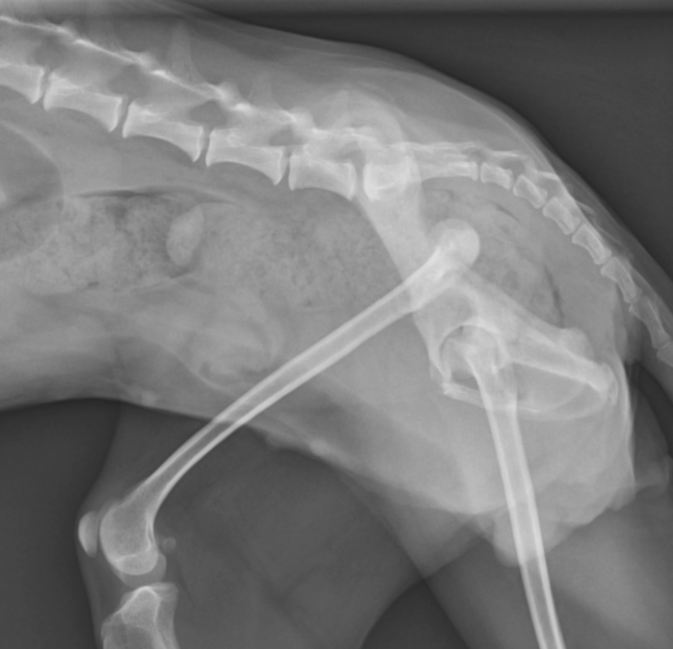

落下や交通事故などにより引き起こされる外傷性と、生まれつき脱臼があり、成長期には症状が現れる先天性があります。

症状は、肘関節形成不全と同様、頭を上げ下げする歩き方や、前足を地面につけない、足が変な方向に曲がってるなどがあります。

外傷性は受傷後速やかに外科的な治療が必要になりますが、先天性は治療が必要にならない場合もあります。いずれも正確な診断が必要になります。

肩関節脱臼は、重度の外傷などで起こるケースがほとんどです。ただ、トイプードルなどは稀に先天的に肩関節形成不全があり、脱臼を発症しやすい子達がいます。この子達は症状が軽度〜重度で様々です。

この脱臼は非観血的に整復したとしても再脱臼を起こしやすく、その場合は外科的な治療が必要になります。